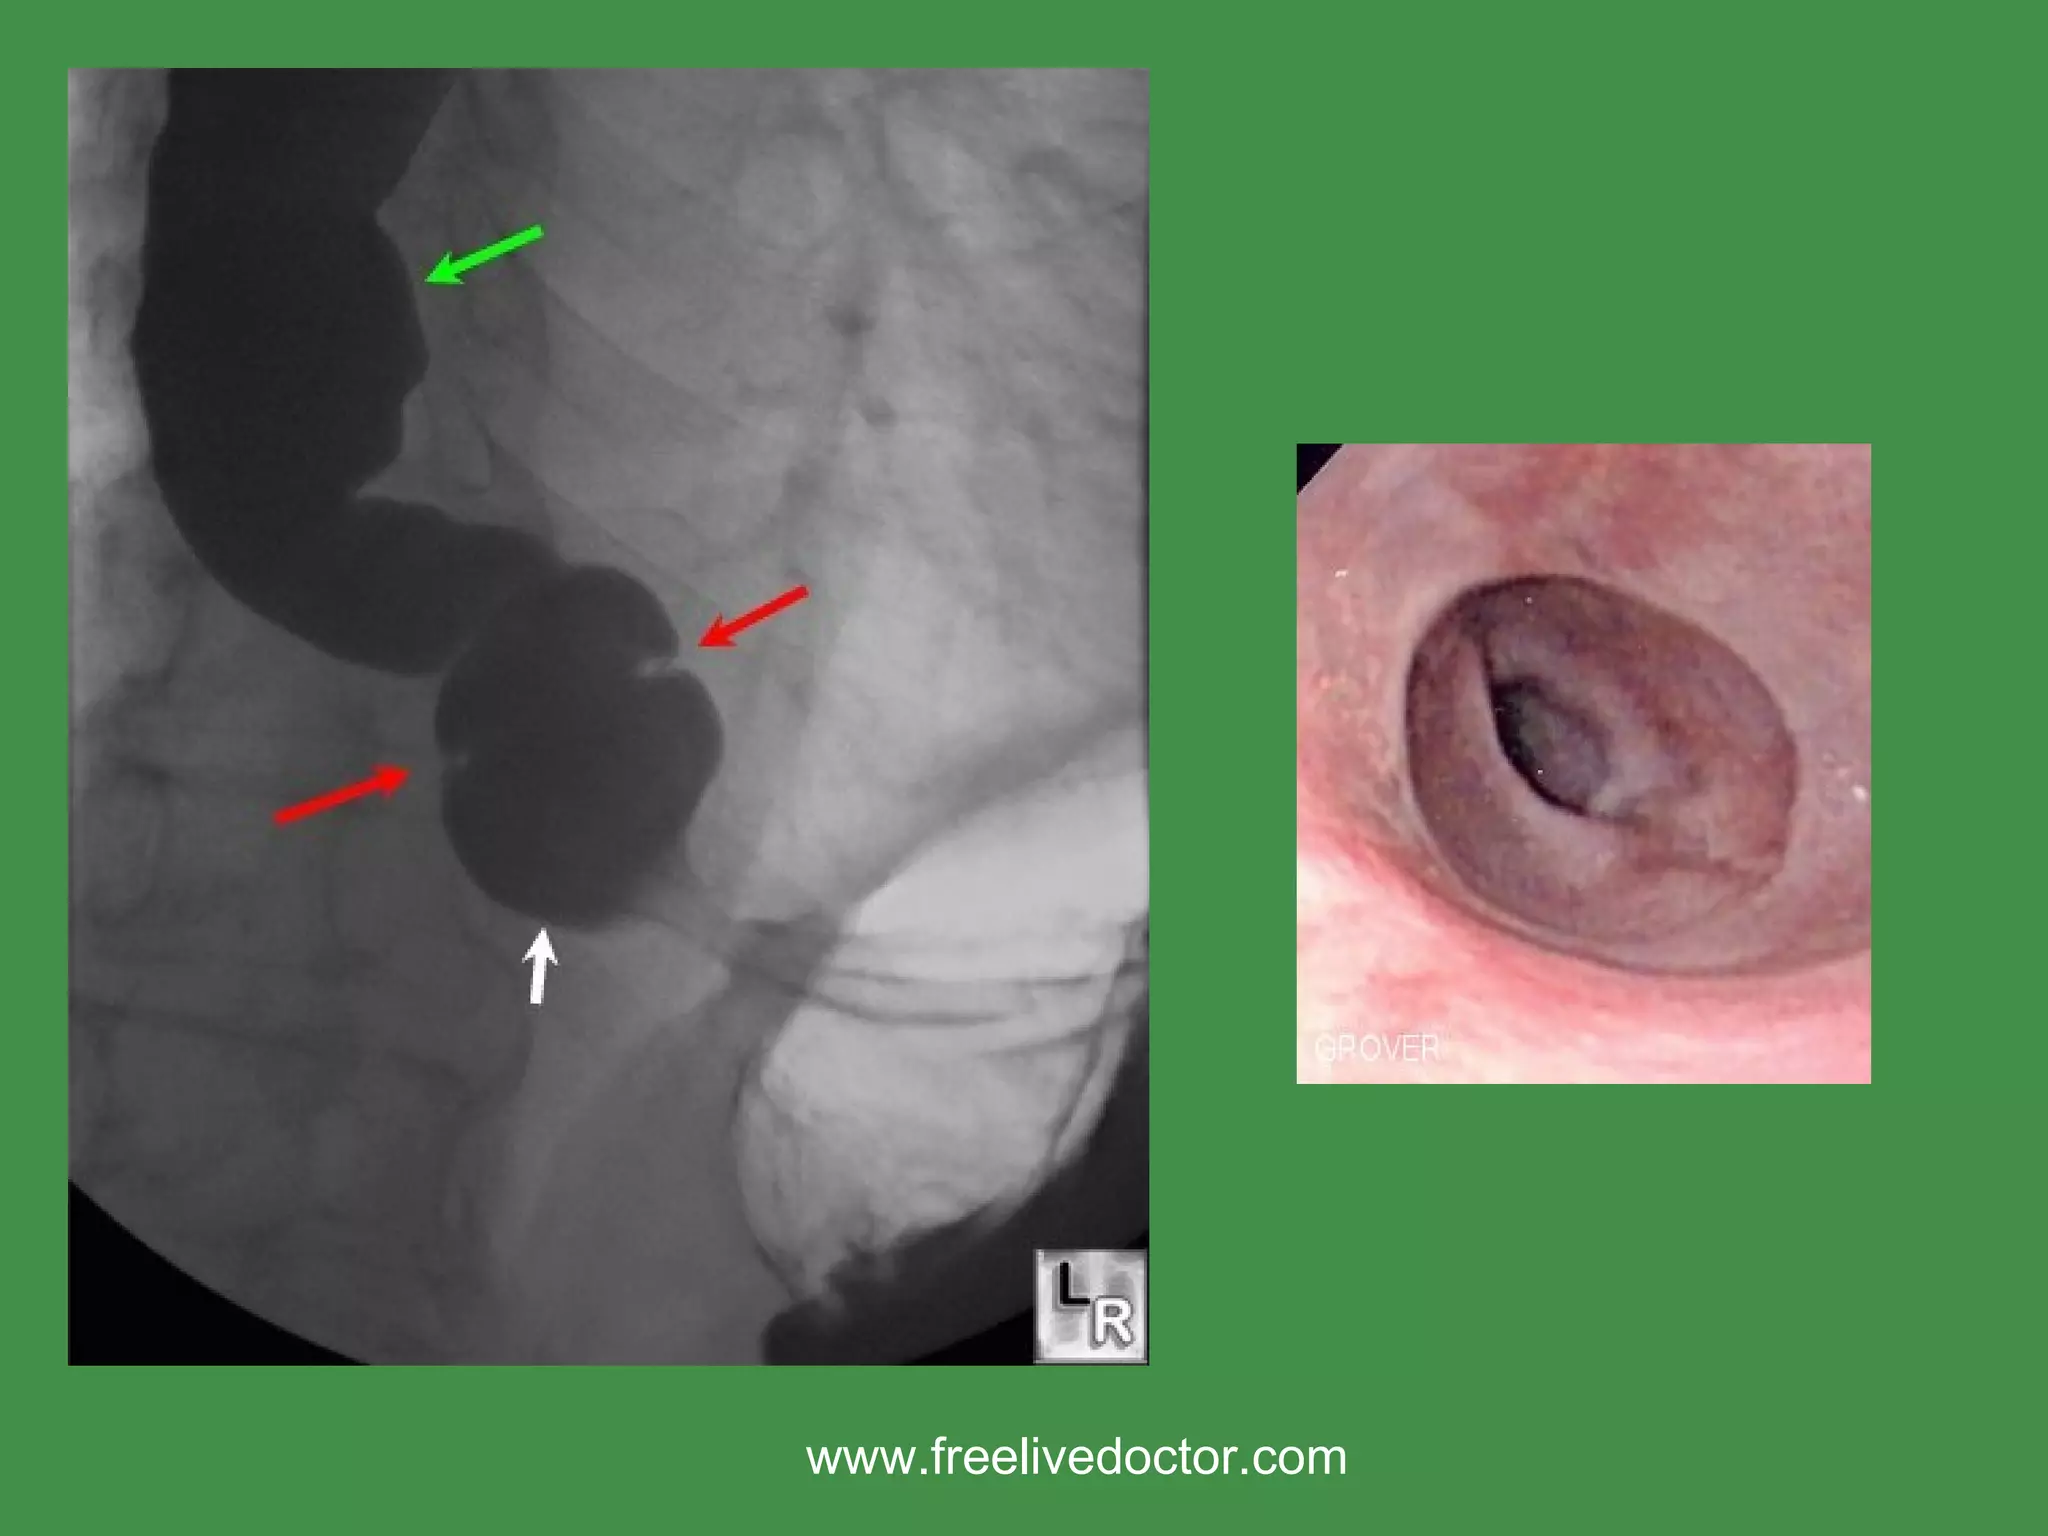

CONGENITAL ANOMALIES ECTOPIC TISSUE (gastric, sebaceous, pancreatic) ‏ Atresia/Fistula/Stenosis/”Webs” Schiatzki “Ring” MOST COMMON www.freelivedoctor.com

• #14 Hiatal hernia with SHATZKI ring.

• #18 Note that the image on the right is the NON-microscopic demonstration of a squamo-columnar junction.